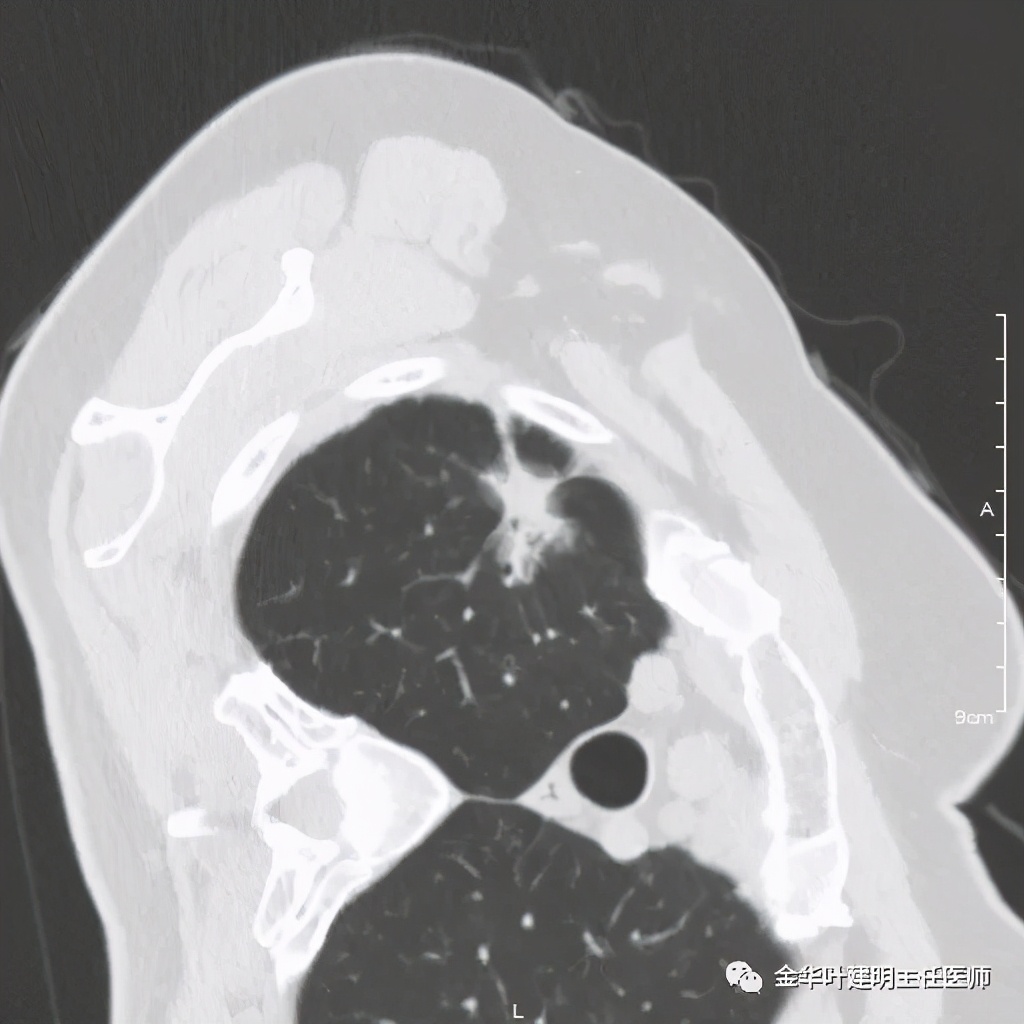

七、浸润性腺癌的其他型:

上图病例为实性,病理上实体型占80%,腺泡型占20%

上图此例也是实性结节,病理报告:实体型伴神经内分泌;

上图此例的实性肿块,病理是:微乳头为主,部分实体型,当时没注明占比;

上图此例实性结节,是实体型,我们发现其影像特征: 病灶有浅分叶、细毛刺、支气管截断征、膨胀性,密度高而密 (比腺泡型实、比粘液癌高、比鳞癌或小细胞癌更具膨胀性)。

但是上面这几例,因为不管怎样的组合,都是实性密度+实性密度,这时仅从影像上就非常难以判断具体的亚型,不过,我们要根据相关的影像特征判断它为恶性,而且该尽早取得病理依据,能手术的要抓紧、不能手术的也要穿刺等得到病理类型的确诊后积极治疗,这就够了!